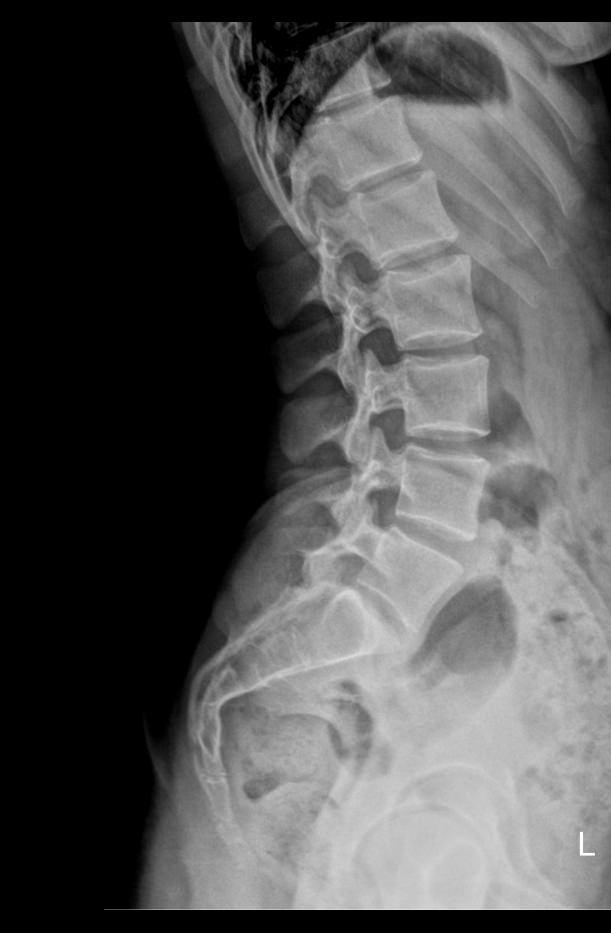

Иногда случаются ситуации, когда боль в пояснице есть, а изменений на стандартных снимках нет. Это связано с тем, что разрушения еще незаметны. Они вызваны врожденной слабостью соединительной ткани и аномальным строением позвонков, недавними травмами, привычной неудобной позой, спортивными и профессиональными перегрузками, а также возрастными изменениями. В любом случае происходит смещение позвонков и сдавливание нервных окончаний, присоединяется местное воспаление. Для выявления начавшегося смещения и разработаны функциональные рентгеновские пробы.

В исследование входит 3 снимка, показывающих состояние поясничного отдела в разных положениях. Однако бояться чрезмерного облучения не стоит: цифровые модели рентгеновского оборудования последнего поколения излучают минимально необходимую для четкого снимка дозу. После данного исследования количество облучения, полученного организмом, будет составлять едва ли десятую часть от допустимой годовой дозы.

На первом снимке будет видно, сохранен ли естественный поясничный лордоз или есть его изменения. На тестовых снимках будут видны:

• Изменение высоты межпозвонковых дисков при отсутствии патологий;

• Неизменность межпозвонковых пространств при наличии функционального блока;

• Смещение позвонков вперед или назад (вправо или влево) при их патологической подвижности;

• Деформация передней стенки позвоночного канала, когда подвижный позвонок смещен кпереди или кзади (вправо, влево).

Также будут видны остеофиты, опухоли, аномалии развития.

Процедура выполняется без подготовки. Пациент раздевается до белья, надевает защитный фартук и встает к пластине детектора. Чаще всего нужно определить смещение в передне-заднем направлении, поэтому пациент встает боком и поднимает руки за голову или держится ими за стул. Выполняется 3 снимка:

• В привычном  положении, то есть обычный боковой;

• В условиях максимального разгибания назад;

• В условиях сгибания вперед.

Реже требуются пробы для определения бокового смещения позвонков. Вы встаете к пластине спиной и, после снимка в прямой проекции, поочередно наклоняетесь вправо и влево. В запущенных случаях при сильной боли и невозможности выполнять пробы стоя, их делают сидя или лежа. Рентгенолаборант поможет вам правильно встать или лечь и безопасно наклониться. Каждый снимок длится около 1 секунды, во время съемки нельзя двигаться, но можно дышать.